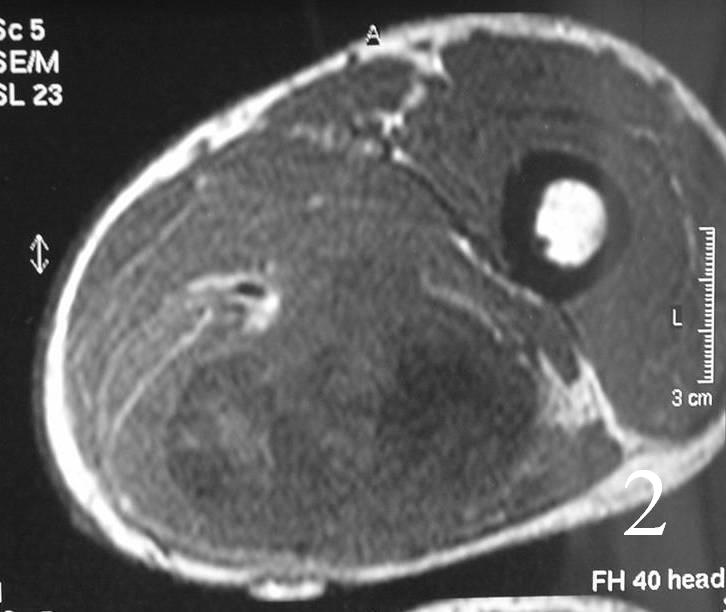

- Isointense to higher signal than muscle on T1W (Fig. 2, 3)

MRI of the thigh, showing a heterogeneous soft tissue lesion in the posterior compartment of the thigh on axial (Fig. 2) and coronal (Fig. 3) T1W images. The addition of gadolinium contrast shows enhancement in the periphery of the mass with necrosis and hemorrhage in the center of the mass typical of a high grade sarcoma (Fig. 4 and 5)